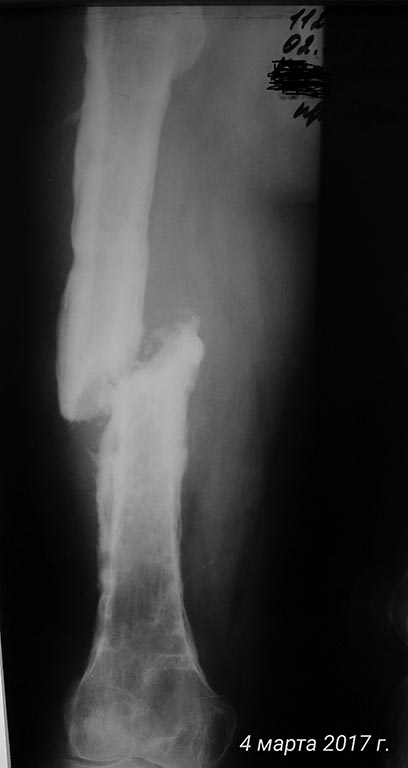

[Ortho] хронический остеомиелит с/3 бедра, свищевая форма, стадия обострения. Несросшийся перелом с/3 бедренной кости.

Дополняю рентген архив

Имя     : P_20170304_124421_1_p.jpg